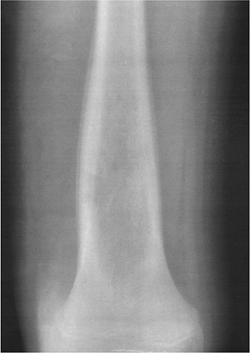

Bone Tumors/Tumorlike Conditions: Adamantinoma

Adamantinomas account for less than 1% of all malignant bone tumors. Patients present with local pain.

-

Age: 74% in the second and third decades

Sex: no sex predilection

Common locations: tibial diaphysis (90%)

Imaging features:

Radiographic features: eccentric lytic

areas with sclerosis. Bone expanded. Typically dominant central lesion.

May be multiple. Both the tibia and fibula may be involved. -

CT: defines cortical and soft tissue involvement

MRI: features variable and not well documented

Differential diagnosis:

Fibrous dysplasia

Fibroma

Treatment: excision with wide margins

P.698

![]() |

|

FIGURE 10-35 Adamantinoma in a 21-year-old man. (A) Radiograph showing a lytic expanding lesion with cortical involvement in the midtibia. Sagittal T1-weighted (B) and axial T2-weighted (C) images showing a muscle intensity lesion on T1-weighted (B) and high-intensity lesion on T2-weighted (C) MR images.